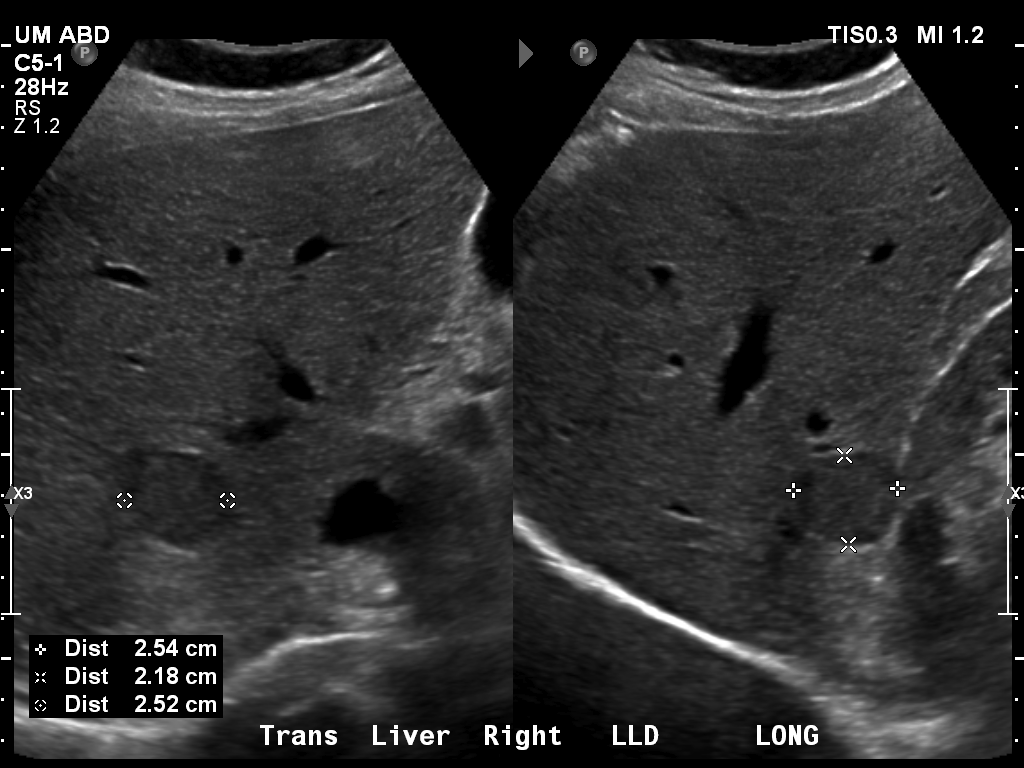

69 M with PMH of HCV cirrhosis & HCC s/p resection in 14 years ago presenting today for a screening ultrasound.

135/73 mmHg / 78 bpm / 16 breaths/min / 96.4°F

sclerae anicteric, no jaundice

CMP wnl, AFP 5